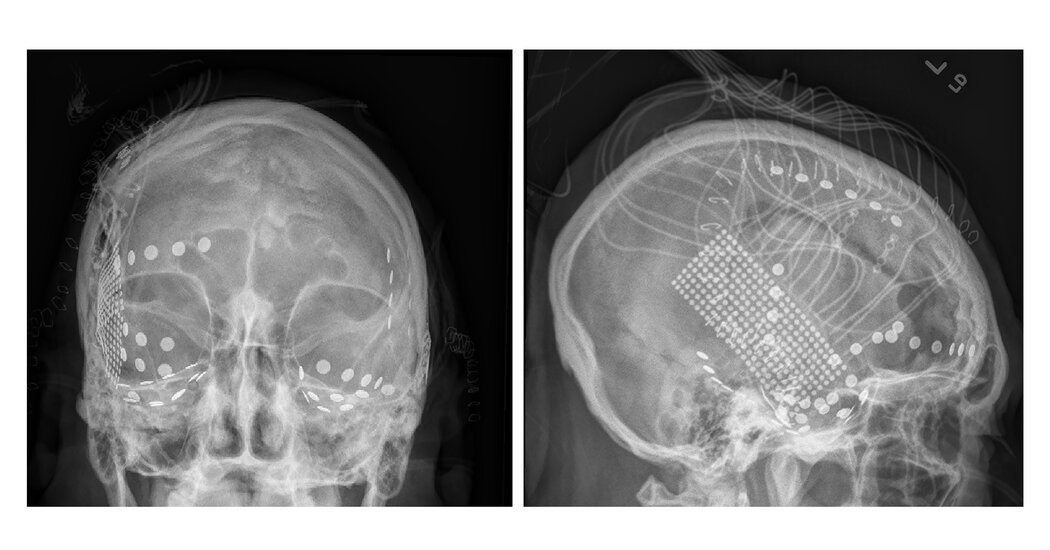

As part of their epilepsy treatment, the patients had a net of nail-like electrodes implanted in their brains. This created a rare opportunity for the neuroscientists to record from their brain activity while they listened to music.